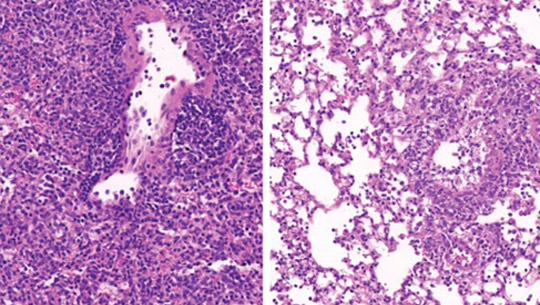

El tejido pulmonar de un ratón diabético (derecha) contiene menos células inmunitarias (pequeños puntos morados) que el de un animal no diabético (izquierda).(crédito de la foto: INSTITUTO DE CIENCIA WEIZMANN)

Se sabe desde hace décadas que los diabéticos y prediabéticos con niveles elevados de azúcar en sangre (hiperglucemia) tienen un riesgo sustancialmente mayor de desarrollar enfermedades pulmonares graves si se infectan con virus como la gripe, así como con bacterias y hongos.

Este misterioso fenómeno se volvió aún más apremiante cuando la pandemia de COVID-19 comenzó a principios de 2020. Quedó claro que los diabéticos estaban en una situación mucho más grave. mayor riesgo de contraer una enfermedad pulmonar grave, incluso mortal, después de desarrollar una forma grave del virus. Sin embargo, nadie entendió por qué. De hecho, alrededor del 35 % de las víctimas del coronavirus que murieron durante la pandemia tenían diabetes.

Ahora, una investigación realizada en el Instituto Weizmann de Ciencias en Rehovot ha revelado cómo, en los diabéticos, los niveles elevados de azúcar en sangre alteran la función de subconjuntos de células clave en los pulmones que regulan la respuesta inmune. También identifica una estrategia potencial para revertir esta susceptibilidad y salvar vidas.